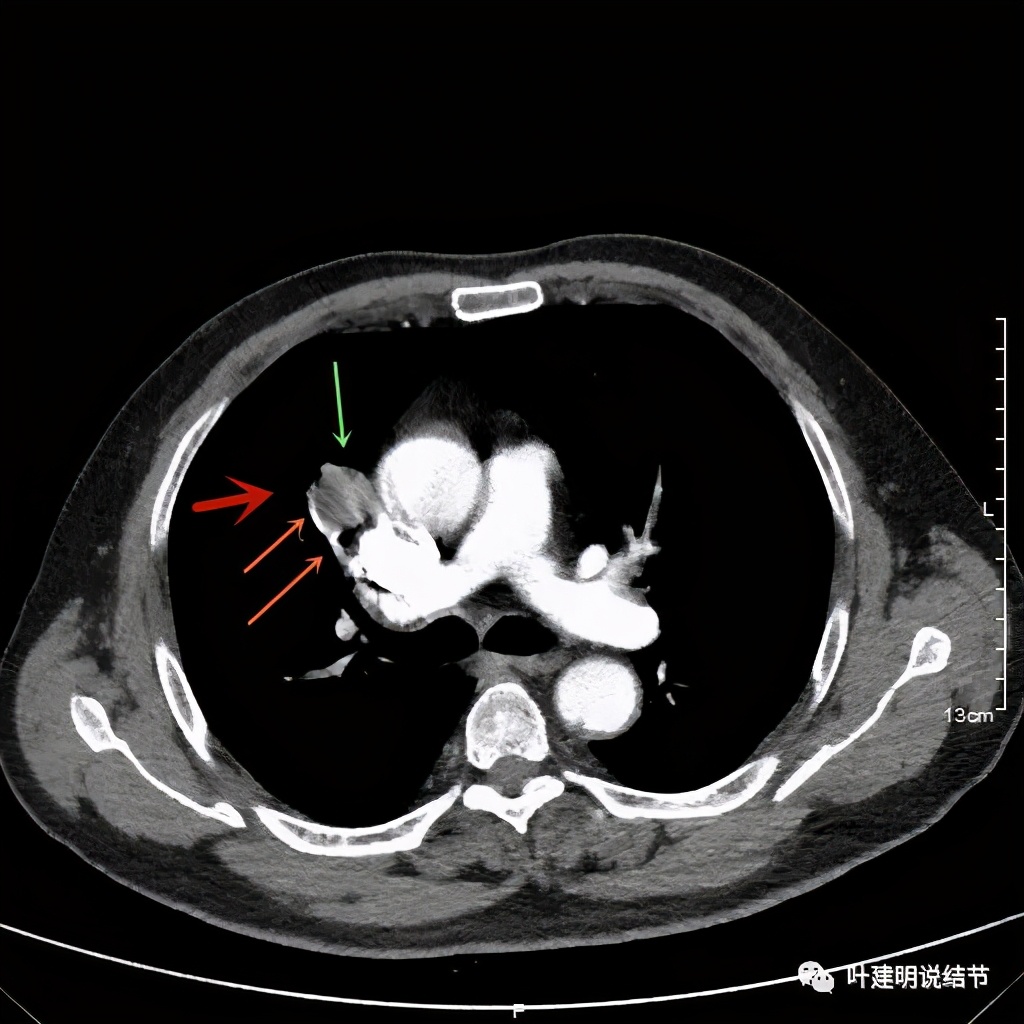

病灶在上图层面似见支气管也是贴壁的。那么增强后又是如何呢?

上图示病灶边缘过于光滑(绿色);局部有点状钙化(蓝色)

上图示病灶边缘过于光滑(绿色);血管贴边(桔色);

上图示病灶边缘过于光滑(绿色);血管贴边走行(桔色)

以上几图也示病灶边缘过光(绿色);血管贴边,感觉没受侵犯(桔色)